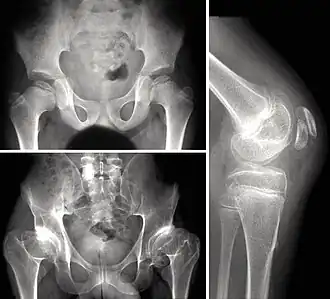

Dysplasie polyépiphysaire

La dysplasie épiphysaire multiple ou maladie de Fairbank est une chondrodysplasie caractérisée par une atteinte des épiphyses, responsable de douleurs articulaires précoces, d'ostéochondrites répétées et d'arthrose précoce[1].